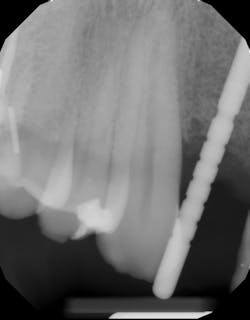

A quick clinical intervention to rectify incorrect initial osteotomy preparation can be accomplished with a Lindemann bur. A Lindemann bur is a side-cutting bur used to move pilot preparation in a bodily manner with ease and without the likelihood of further angulation issues (figure 4). After initial pilot drilling, a radiographic locator is placed to check position. If the radiographic index is shown to be incorrect, under copious irrigation, place a Lindemann bur in the osteotomy parallel to the intended location and move in a rigid upright fashion to the ideal location. Take a radiograph to verify correct position.